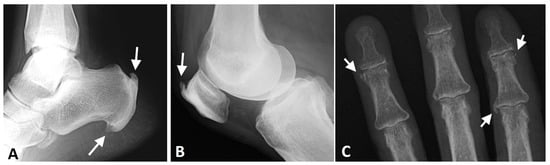

Figure 9.

Radiographs of the ankle, knee, and hand of a patient with thoracic DISH (not shown). (A) Lateral radiograph of the ankle, showing coarse, thick enthesophytes in the attachment of the Achilles tendon and plantar fascia to the calcaneus (arrows). (B) Lateral knee radiograph showing thick, coarse enthesophytes (arrow) in the attachment of the quadriceps tendon to the patella. (C) AP radiograph of the fingers, showing enthesophytes in the medial side of the 2nd metacarpophalangeal joint and 4th distal interphalangeal joint and the lateral side of the 2nd distal interphalangeal joint (arrows).